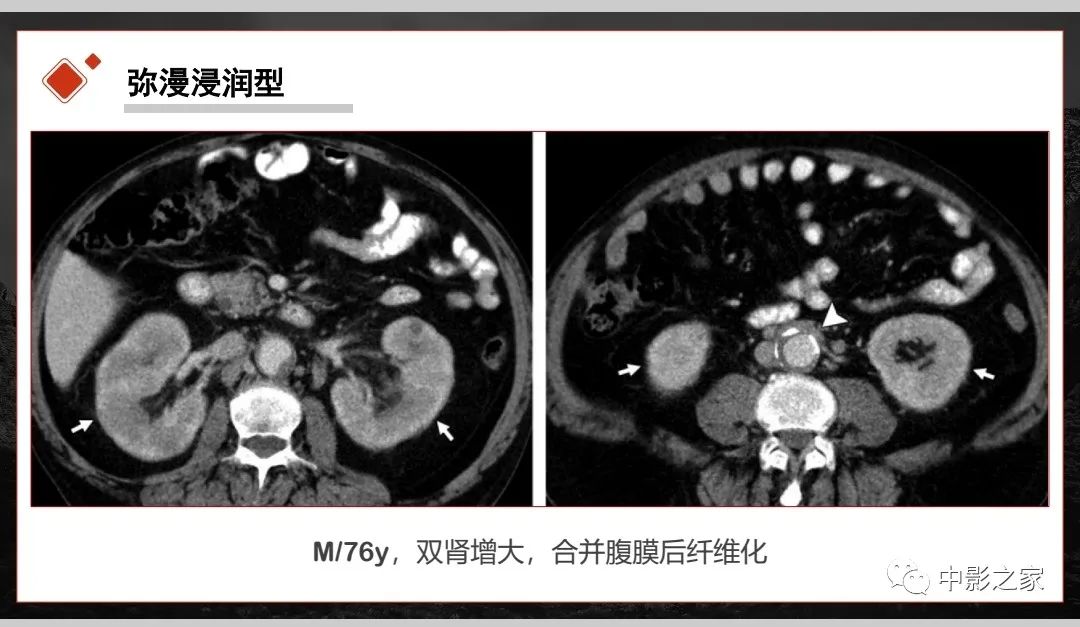

肾脏IgG4-RD临床、病理及影像特征